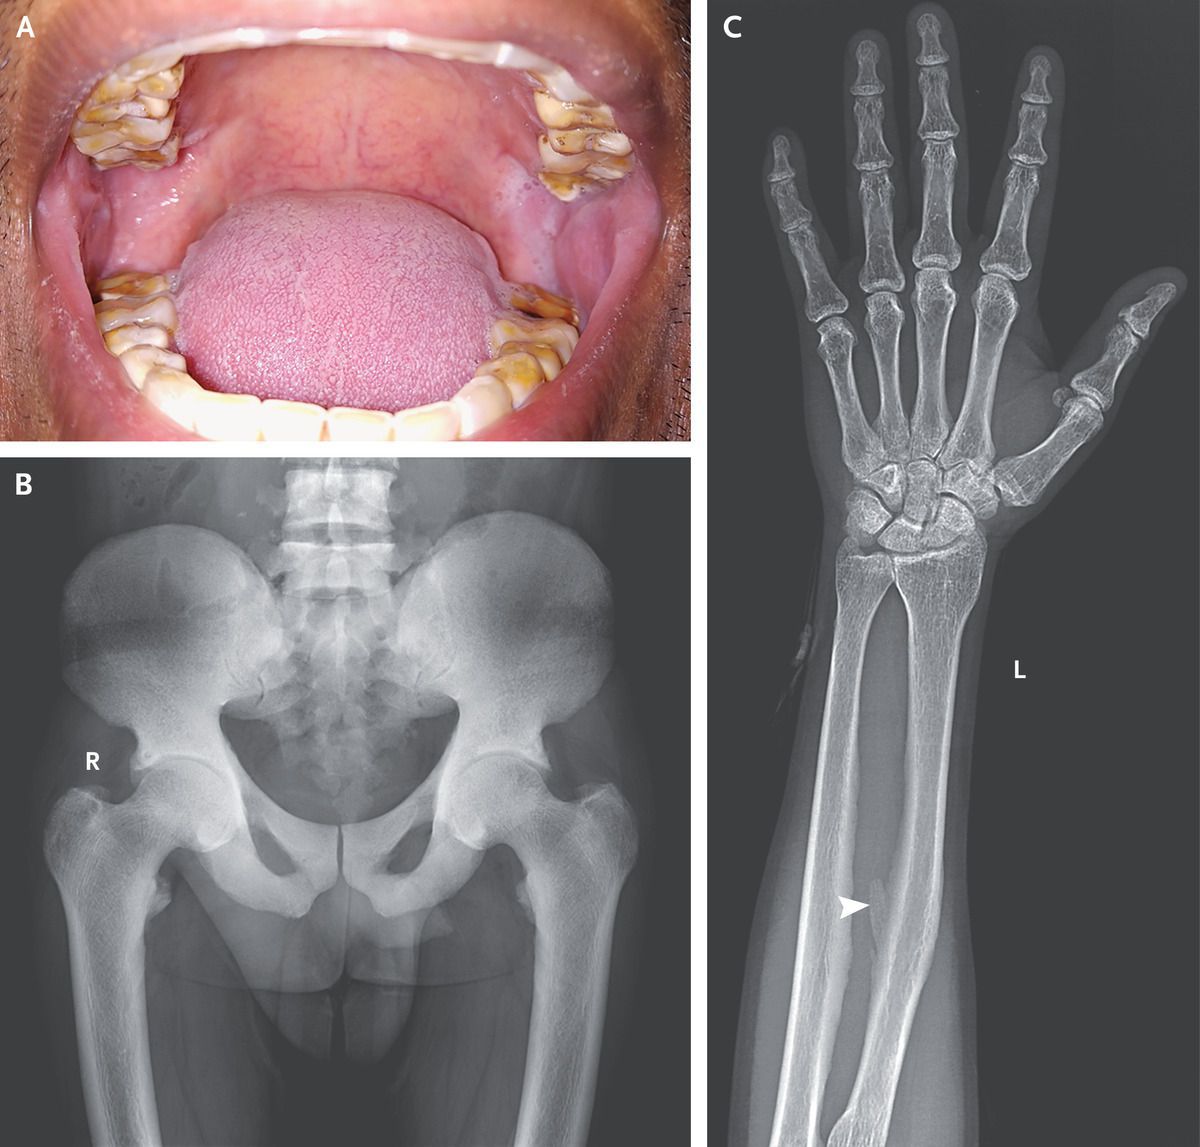

A 32-year-old man presented to the rheumatology clinic with a several-year history of lower back pain and stiffness of the neck, shoulders, and hips. On examination, he had yellowish-brown tooth discoloration (Panel A) and restricted movements of the cervical spine, hips, and shoulders. Pelvic radiography showed osteosclerosis without sacroiliitis (Panel B). T scores for bone mineral density were +12.1 at the lumbar spine and +3.1 at the hip. Laboratory tests showed an alkaline phosphatase level of 479 IU per liter (reference range, 80 to 240) and a parathyroid hormone level of 103 pg per milliliter (reference range, 15 to 68), with normal levels of creatinine, calcium, and vitamin D. Since the patient lived in an area with high levels of fluoride in the groundwater, skeletal fluorosis was suspected. Radiography of both forearms showed interosseous membrane calcification (Panel C, arrowhead). The serum fluoride level was 0.05 ppm (reference value, <0.02 ppm), and the 24-hour urinary fluoride excretion was 7.5 ppm (reference value, <0.1 ppm), which confirmed the diagnosis. He was advised to defluorinate his drinking water and was treated with calcium, vitamin D, and nonsteroidal antiinflammatory drugs. Two years later, he reported a 50% reduction in pain and stiffness.